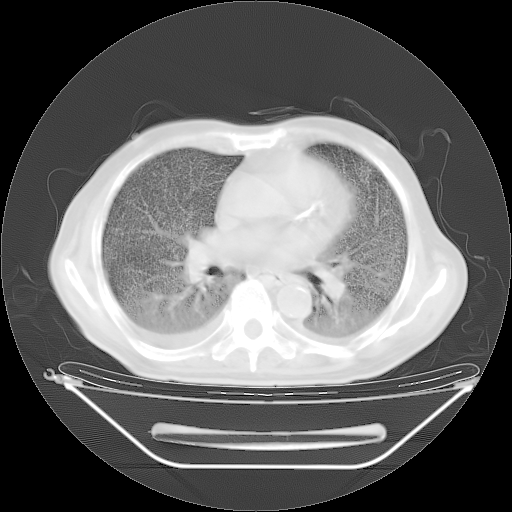

今天复查肺部CT,发现双肺广泛磨玻璃样改变。所以我把3月19日和5月9日相隔50天的肺部CT上传。请大家会诊。

5月9日肺部CT(在4月27日齐鲁医院肺部CT描述部分肺组织磨玻璃样改变,12天后肺组织广泛磨玻璃样改变)

2009年5月9日肺部CT

大致读了系列胸部CT:纵隔窗无明显异常,肺窗:从4、27至今:主要是双肺中下野外带可见毛玻璃样改变,目前处于急性肺泡炎阶段,至于原因考虑1、结替组织或胶原血管性疾病所致?2、恶性疾病如恶组在肺部所致的表现或细支气管肺泡癌?3、药物或其它原因如肺蛋白沉着症所致肺泡炎目前不太可能?总之,明天就去请我院的呼吸科、感染科、血液科和临免专家会诊哈。